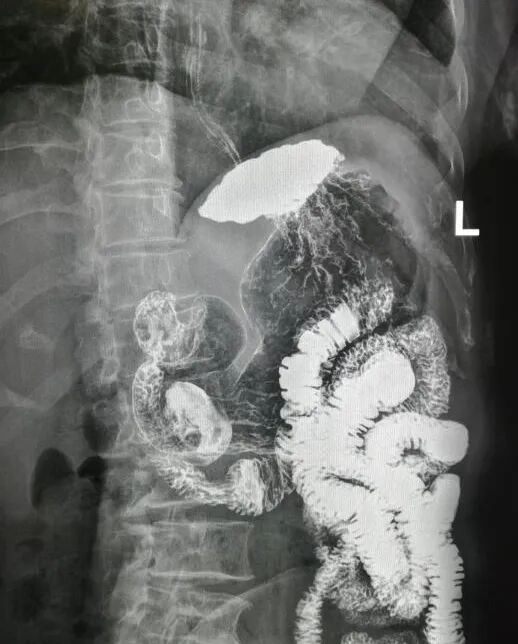

福利来了全套消化道钡餐图食管胃小肠结肠直肠